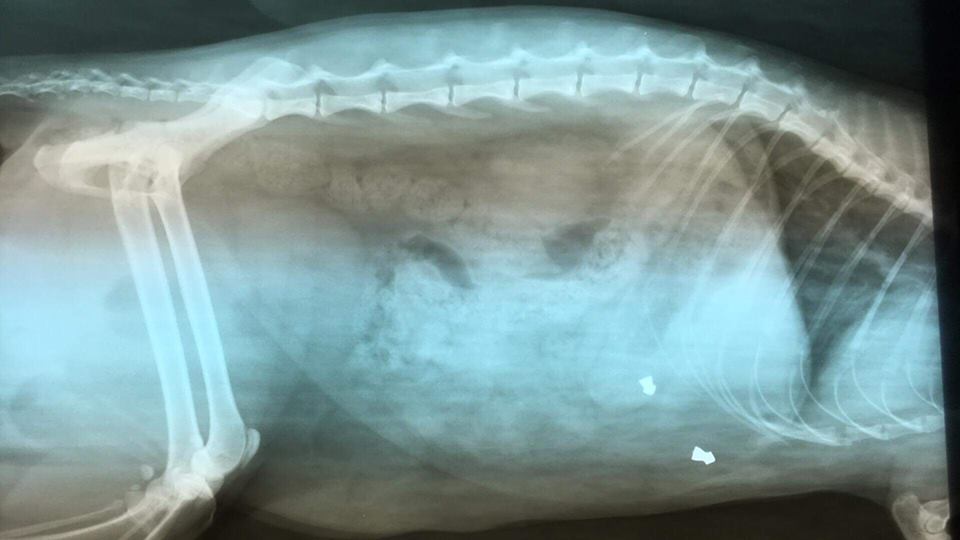

Na portalu społecznościowym na stronie należącej do jednej z przychodni weterynaryjnych na os. Ustronie pojawiła się informacja, iż nieznany sprawca z broni na śrut strzela do zwierząt. To kolejne takie zdarzenie na tym osiedlu. Tym razem kilkukrotnie został trafiony kot z ulicy Asnyka.

fot: fb Przychodnia Weterynaryjna lek.wet Mariusz Konarski Lubin ul.Norwida 42